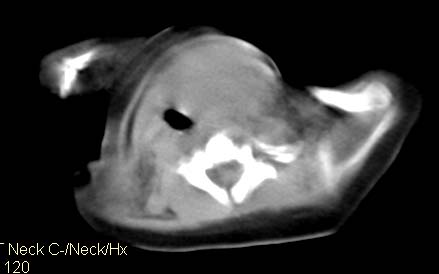

男,26天,发现左侧颈部包块5天,质较硬,患儿不哭不吵,无明显发热,头向右侧歪斜,其父母诉患儿出生时正常,昨天查血象wbc19.4×10的9次方/l,b超考虑来源于甲状腺的恶性肿瘤,我科认为肿块内有低密度区,而且病程发展较快,血象高,考虑炎性病变可能大。患儿年龄太小没做增强。请大家提出高见。

男,26天,发现左侧颈部包块5天,质较硬,患儿不哭不吵,无明显发热,头向右侧歪斜,其父母诉患儿出生时正常,昨天查血象wbc19.4×10的9次方/l,b超考虑来源于甲状腺的恶性肿瘤,我科认为肿块内有低密度区,而且病程发展较快,应该首先排除血肿,其次考虑感染

随访结果:炎症(患儿经过一星期抗炎治疗后颈部包块明显缩小,现已经正常)。